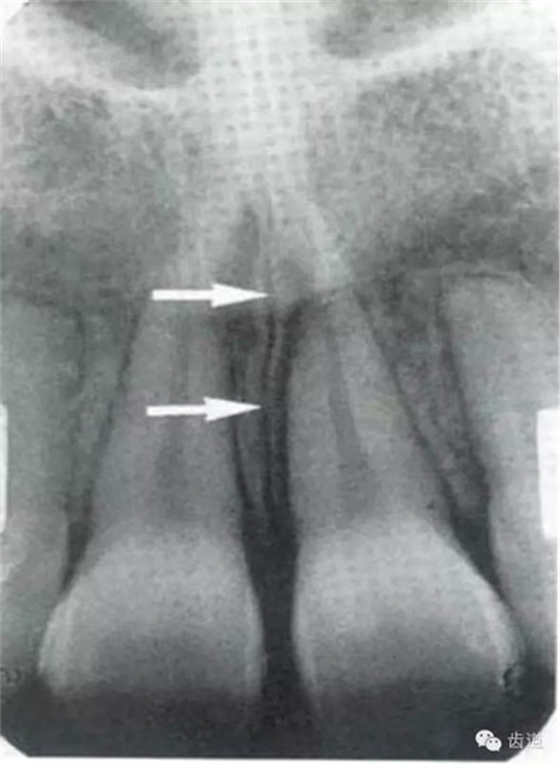

即固有牙槽骨,是牙槽骨的內(nèi)壁,圍繞牙根,骨質(zhì)致密而薄,X線片上顯示為包繞牙根的連續(xù)不斷的密度高的線條狀影像。

是介于牙槽窩和牙骨質(zhì)之間的結(jié)締組織。牙周膜的厚度一般在0.15~0.38mm之間。X線上顯示為包繞牙根連續(xù)不斷的密度低的線條狀影像,其寬度均勻一致